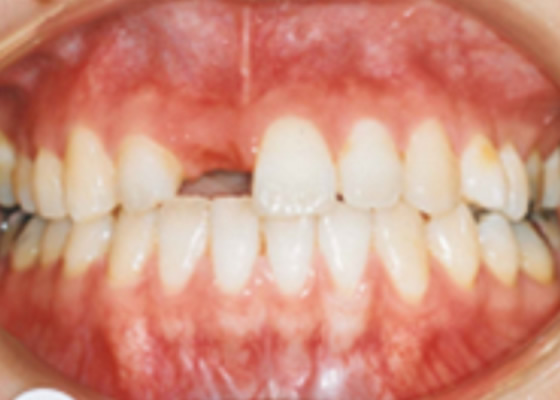

治療内容:前歯部分の欠損と歯を白くしたいという主訴に対してインプラント治療、セラミック治療を行った症例。

治療費:¥220,000~/1本+ハイブリッド冠¥55,000 診断料:¥22,000

副作用・リスク:インプラントオペによる一時的な炎症・出血や顔面の内出血、治療終了後のメンテナンス不足による歯周病やインププラント周囲炎、歯ぎしりや過剰な噛み締めによるセラミックスの破折。